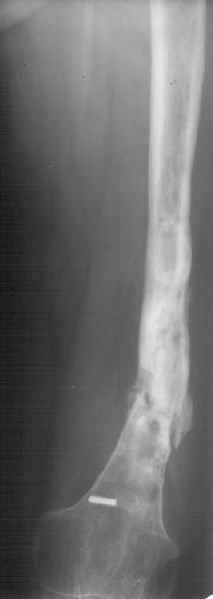

К нам поступила худощавая женщина 48 лет, которой года 2,5 назад был выполнен остеосинтез бедра пластинкой в одной из горбольниц. В сентябре 2001 г. пластинку убрали. Начала разрабатывать движения, ходила с тростью. С января этого года

отмечает усугубление деформации бедра и улучшение движений "в коленном суставе". При осмотре имеетсяподвижность на месте перелома (псевдартроза), больше в сагиттальной плоскости. Рентгенограммы в приложении(фас; профиль). Полностью угол, открытый кзади, под нагрузкой не устраняется. "Сгибается" еще градусов на 30. Ходит с тростью. Надколенник неподвижен, в суставе, видимо, движений нет совсем. В любом случае надо, видимо, начинать с восстановления оси и стабилизации бедра. Как окончательный фиксатор хотелось бы использовать интрамедуллярный стержень. Можно ли в данном случае устранить угол одномоментно? Или лучше дозированно? Нужна ли костная пластика местно? Не стоит ли пойти на мобилизующую операцию в один этап? Если да, то какую?Может быть, есть еще какие-то моменты, которые следует учесть?Спасибо заранее.-- Best regards, Alexander N. Chelnokov